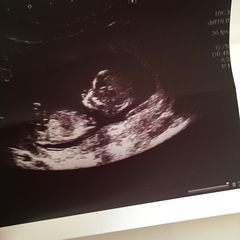

japan I had a read of the nub theory but couldn't quite make mine out! My DH thinks girl, I'm sure I see a boy nub but I've no idea!

December 2017 babies #6 - dating scans, gender reveals, the beginning of bumps & the 2nd trimester!

biginjapan · 06/06/2017 17:30

I'm no expert, but I would guess girl from those. Really not professing to be great at this though!

tuxedocat · 06/06/2017 17:42

Thank you. It's quite fun to see how different all the scans are